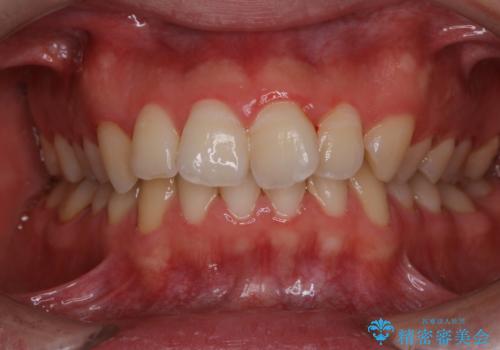

人生で初めての歯のクリーニング

- 今まで歯科でのクリーニングを受けたことがないとのことでした。

PMTC60分コースを行いました。